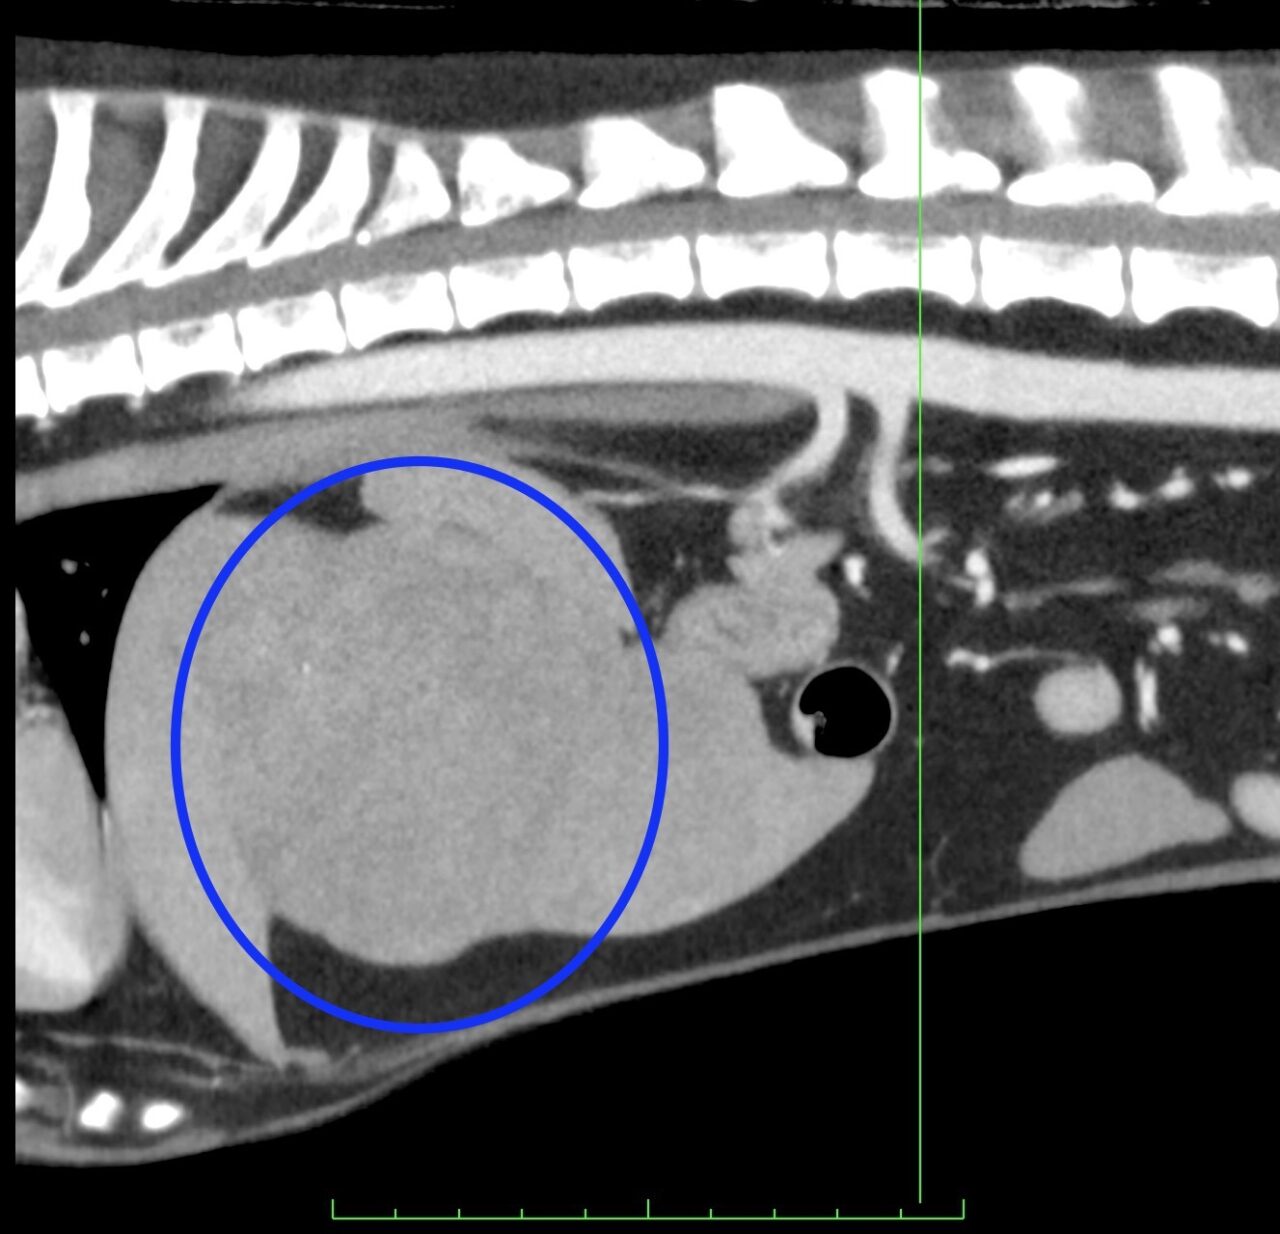

CT所見です。肝臓の左側に大きな塊状病変が認められます。